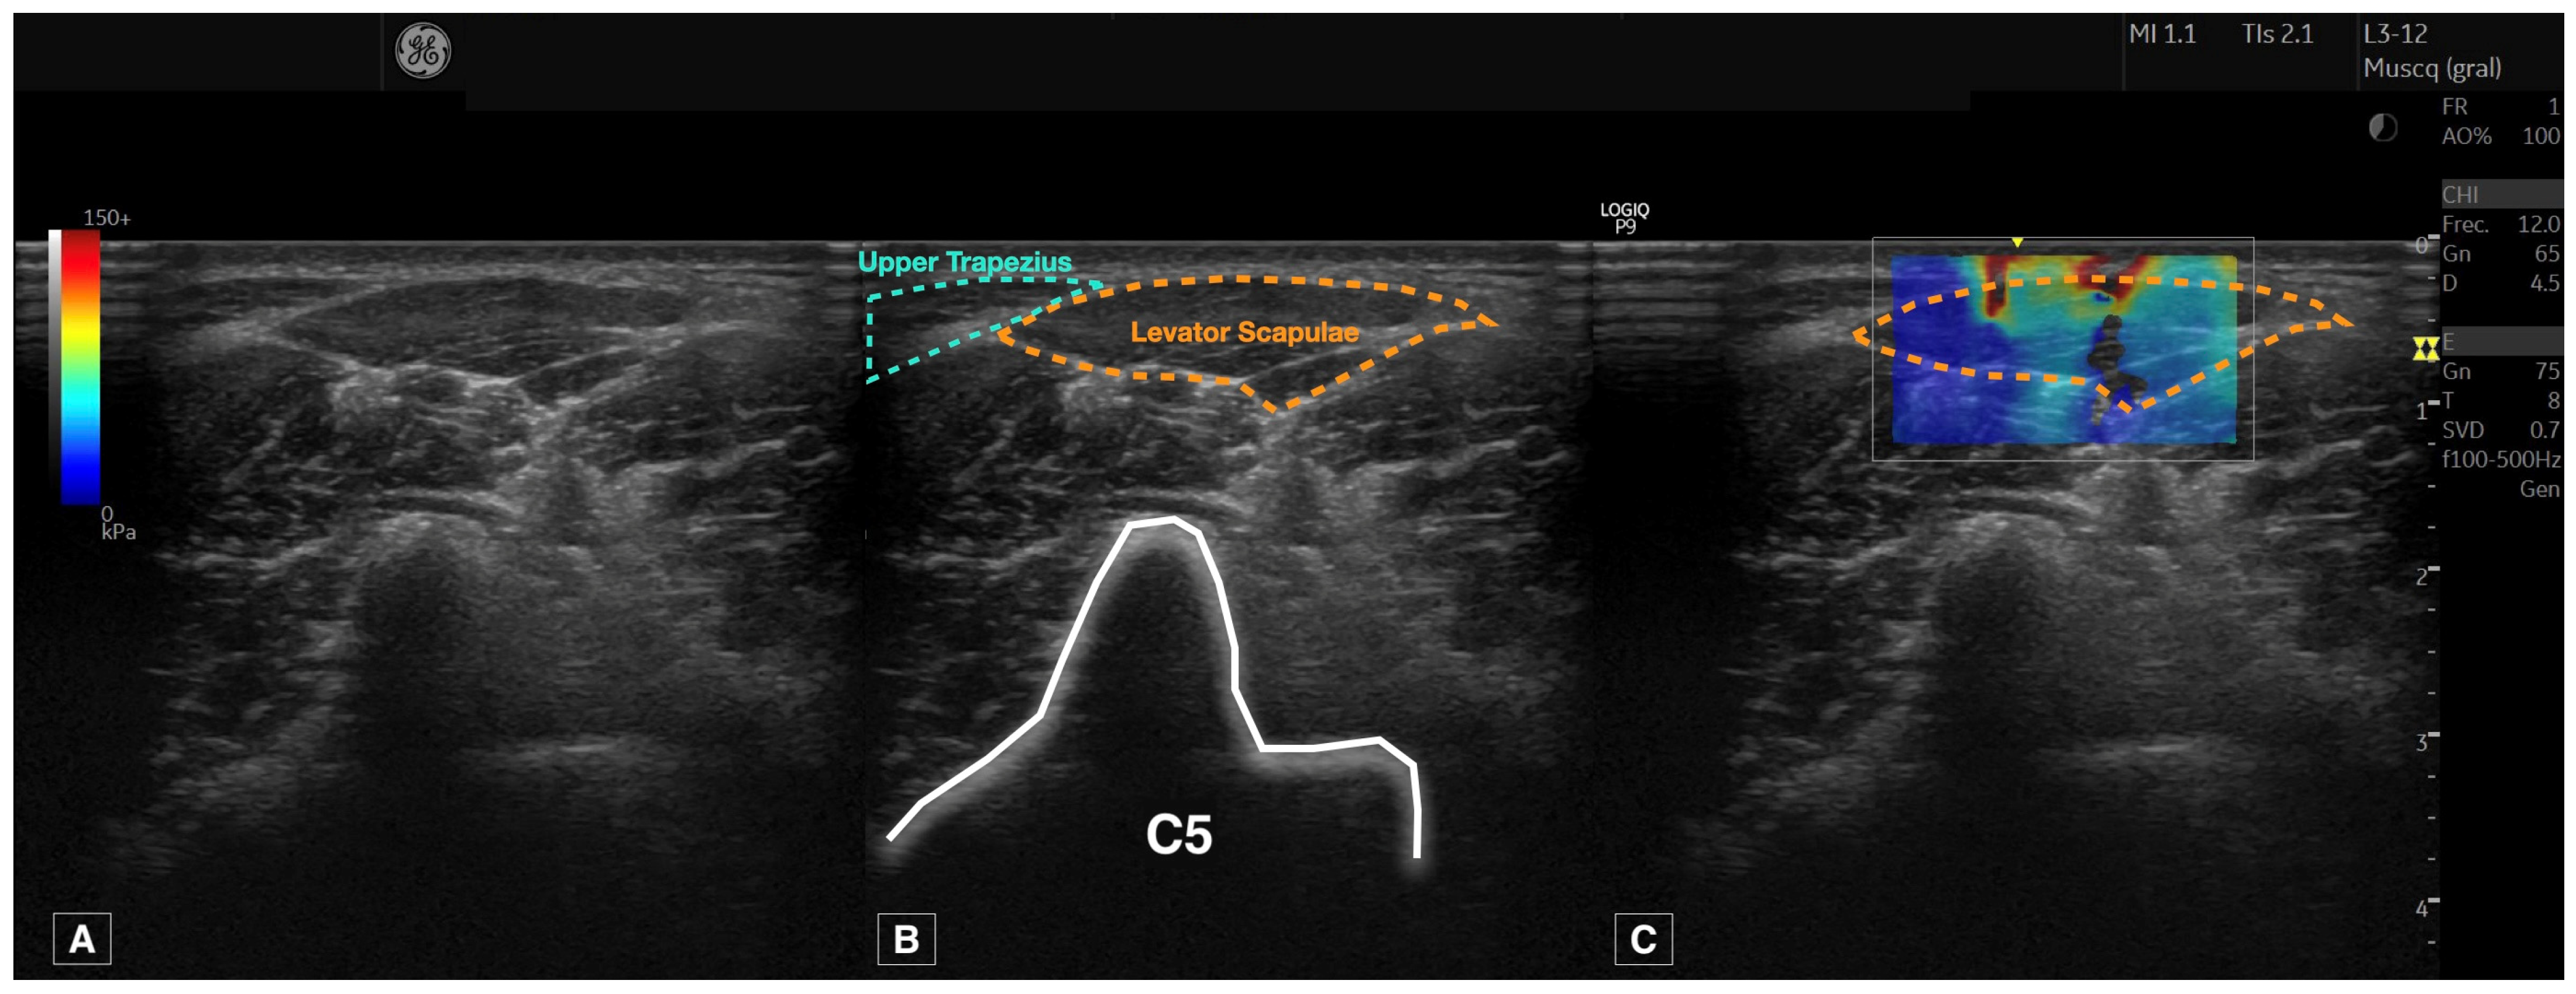

2.5. Ultrasound Imaging Acquisition Protocol

2.6. Measurement of Muscle Stiffness